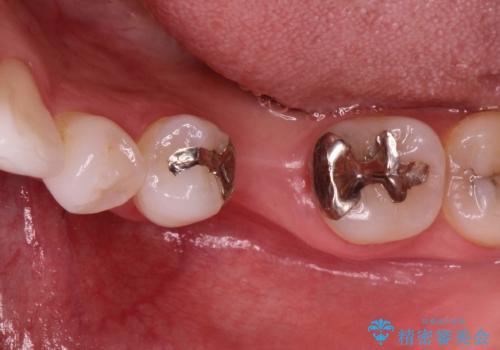

深い虫歯により抜歯となった奥歯 インプラント治療でかみ合わせを回復する

- 保存不可能な歯の抜歯後、待時にてインプラントを埋入、2回法にて咬合回復を計画した。

同時に、前後の歯の金属のやり直しも行った。

今後しっかりとつかっていけるかどうか、予後の悪い歯を、リスクを承知で残すのか、

抜歯をしてインプラントにするのか、

どちらが正しいということはありませんが、後者の方が予測実現性が高く、再治療の可能性は低いといえます。